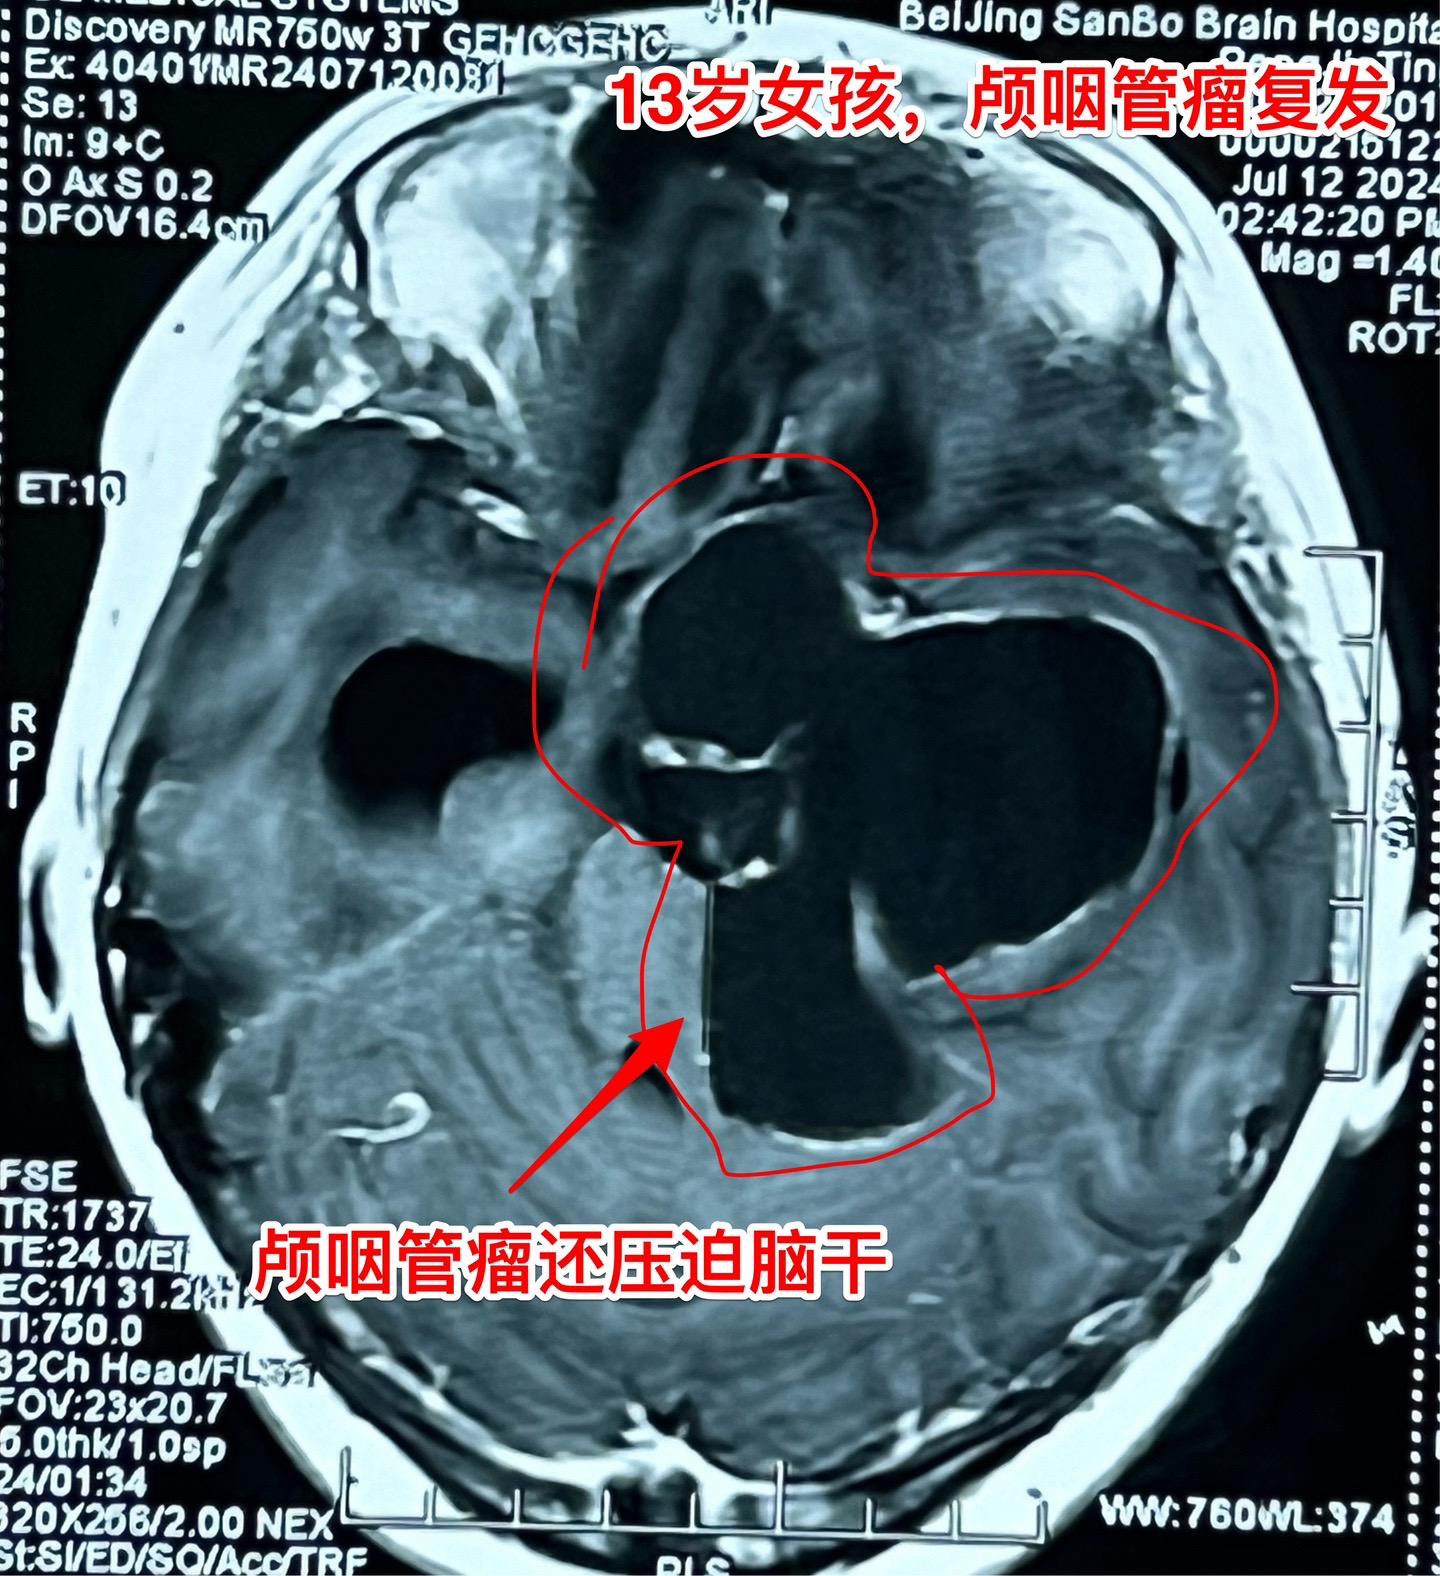

复发的巨大颅咽管瘤,难度很大。13岁四川女孩子,2022年6月在外院行开颅手术切除颅咽管瘤。半年后颅咽管瘤复发,家长采用中药治疗。中药控制颅咽管瘤的效果也不理想,肿瘤还在继续生长。 复发肿瘤体积越来越大,患儿曾经出现过头痛、呕吐、多睡症状。经过补充糖皮质激素后症状有好转。额部骨头逐渐出现隆起,见图4、5。 2024年7月16日作了开颅手术,将颅咽管瘤完全切除。肿瘤体积大,压迫脑干,而且与周围的血管粘连紧密,手术过程很艰难,最终获得完全切除。 手术后患儿很虚弱